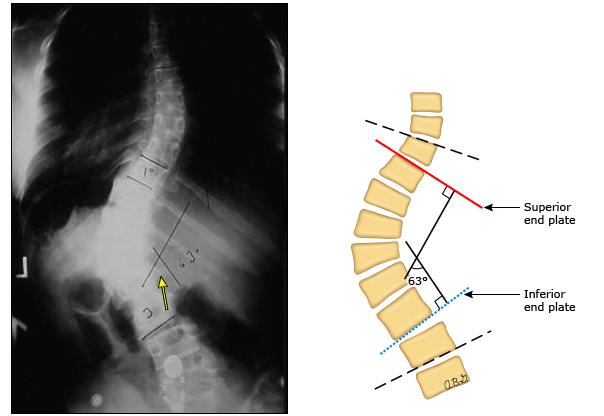

我们评估侧弯有多严重,有个专门的测量方法,即Cobb角,这是在X光片上可以测量出的,如下图。这个角度越大,意味着脊柱侧弯的角度越大,畸形越严重,病情也越复杂。

比如,一般如果cobb角度超过50度,那么即便是再小的孩子,也需要尽快手术矫正。而一般对于角度在20-40度左右的孩子,可以考虑根据年轻酌情选择佩戴支具矫正。而20度以下,尤其是不到10度的侧弯,大多可以密切观察。